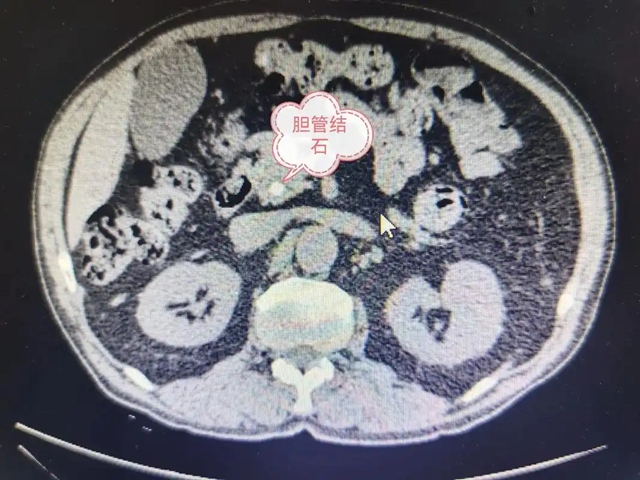

【警惕】感染性休克,藏在胆总管里的“定时炸弹”

一天晚饭后,张大爷因突发剧烈腹痛、高热、精神极差被送进急诊,行腹部CT检查发现是胆总管下端有个小结石堵死了,引起胆总管结石伴急性梗阻性化脓性胆管炎(AOSC)。家属慌了:“不就是胆结石吗?怎么突然要命了?”  张大爷被紧急收入肝胆胰外科住...